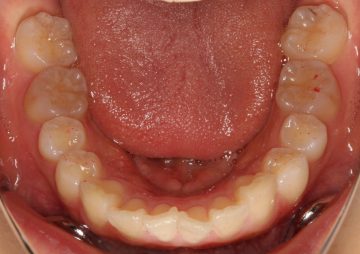

治療前